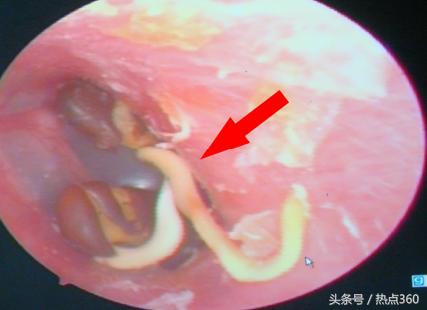

晚报6月份以《幼童塞进左鼻一粒绿豆 军医取出时已经发芽》为题曾报道过一个3岁男孩,无意中将一颗绿豆塞进鼻孔,不久长出绿豆芽的稀罕事。无独有偶,近日,252医院耳鼻喉科护士从一男孩左外耳道取出3棵发了芽的小红豆。如果没有耳内电子窥镜拍照(图1)和取出后的实物照片(图2)作证,很难让人相信。

护士采用耳内电子窥镜进行检查,看到患儿左外耳道有3个异物,异物形状好像是豆芽,感到非常奇怪。护士用镊子谨慎翼翼地将3个异物一一完整取出。经辨认,确认3个异物为3个发芽的小红豆。